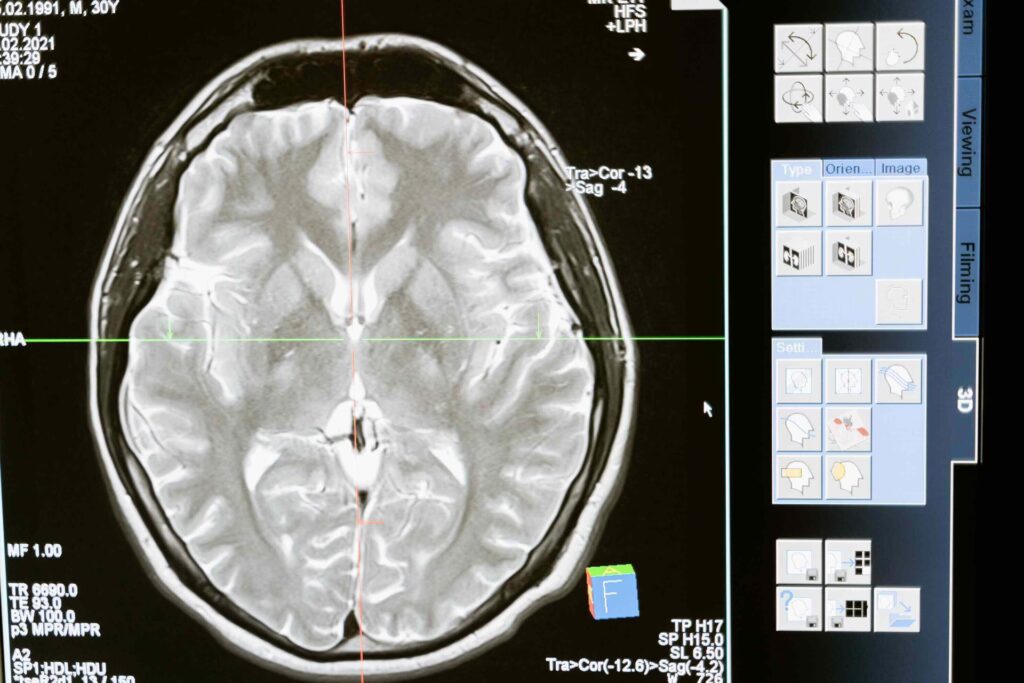

Pasión en el Cerebro: Más Allá de la Química

Más allá de los neurotransmisores, la pasión afecta la actividad de regiones cerebrales específicas. La pasión romántica intensa activa poderosamente el Sistema de Recompensa del cerebro, las mismas áreas asociadas con el placer derivado de comer, beber o incluso el uso de ciertas drogas. Las estructuras relacionadas con los pensamientos obsesivos también muestran una actividad intensa. Esto explica por qué las personas enamoradas pueden sentirse como si estuvieran intoxicadas, experimentando una felicidad extrema y encontrando difícil dejar de pensar en su pareja.

Un hallazgo particularmente interesante es que simplemente mirar una fotografía de la persona amada suprime la actividad en la región del cerebro que controla el pensamiento crítico. Esto respalda la idea de que la pasión inicial puede cegarnos a los defectos del otro, fomentando la adoración.

En las relaciones a largo plazo, que combinan intimidad y compromiso, la actividad cerebral muestra una mezcla fascinante. En estudios con parejas que declaraban seguir profundamente enamoradas después de muchos años, el centro de placer del cerebro seguía activo al ver a su pareja, similar a la etapa inicial de infatuación. Sin embargo, también mostraron una actividad pronunciada en las regiones cerebrales asociadas con el amor parental, sugiriendo que el cuidado y la preocupación por el bienestar del otro se convierten en componentes centrales del vínculo con el tiempo.

Otro estudio longitudinal comparó imágenes cerebrales de parejas al inicio de su relación y tres años después. Aquellas que permanecieron juntas mostraron una actividad reducida en estructuras cerebrales relacionadas con la representación del propio yo en las primeras etapas. Esto sugiere que, en el amor intenso, el concepto de uno mismo se desdibuja y se fusiona con el del compañero. Cuanto más intenso era este fenómeno de "fusión del yo" al principio, mayor era la probabilidad de que la relación durara.